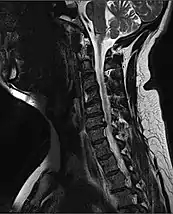

MRI of fractured and dislocated neck vertebra that is compressing the spinal cord